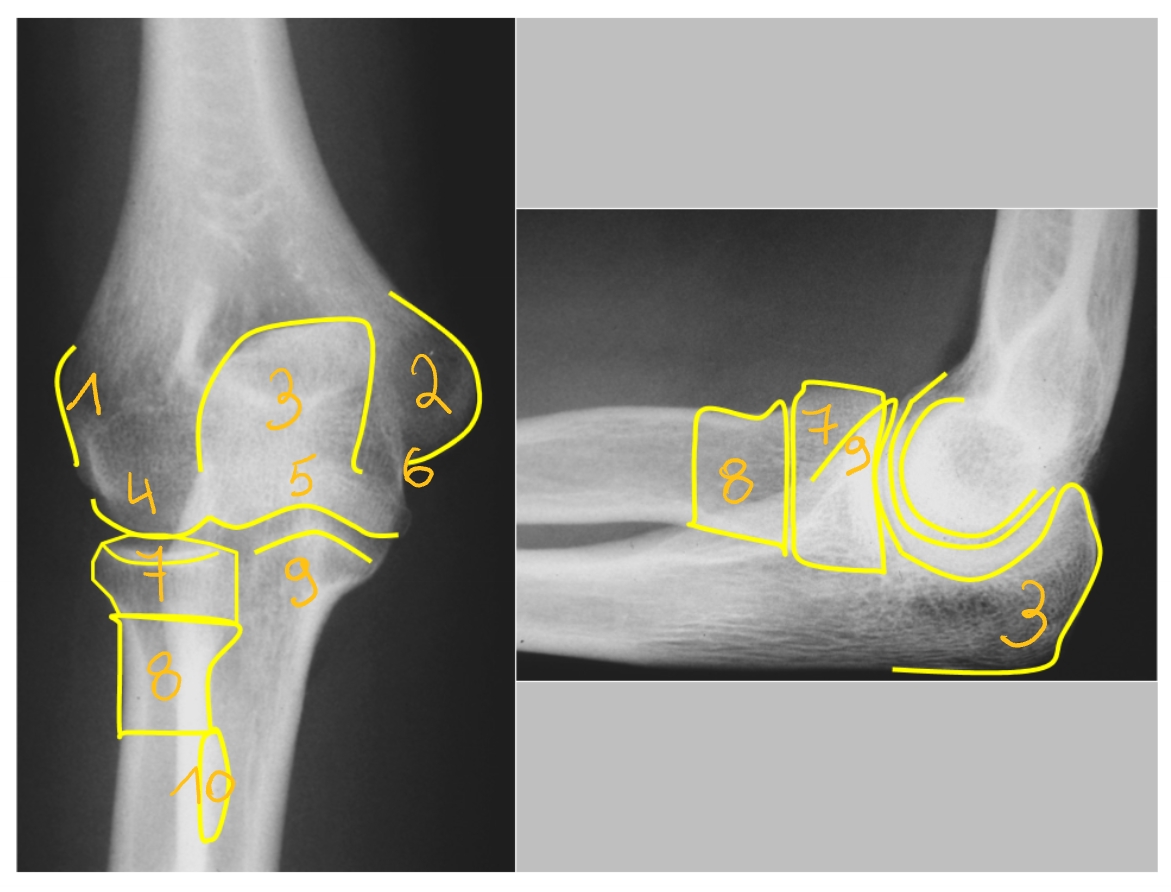

epicondylus radialis/ lateralis

epicondylus ulnaris/ medialis

olecranon

hierop: pees van de m. triceps

capitulum humeri

trochlea humeri

n. ulnaris

caput radii

collum radii

processus coronoideus

insertie van de m. brachialis

tuberositas radii

insertie van de m. biceps

→ rechter elleboog: van voor naar achter